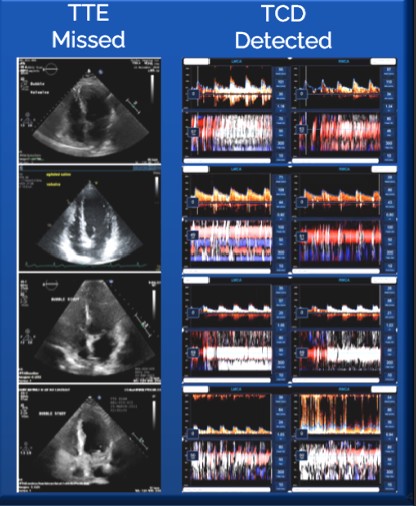

Zašto je TCD bolji za otkrivanje PFO od TTE

• Veća osjetljivost: TCD detektuje mikromjehuriće u arterijama mozga, što daje precizniju procjenu težine šanta.

• Pouzdanije otkrivanje malih šantova: TCD može detektovati i male šantove koje TTE može propustiti.